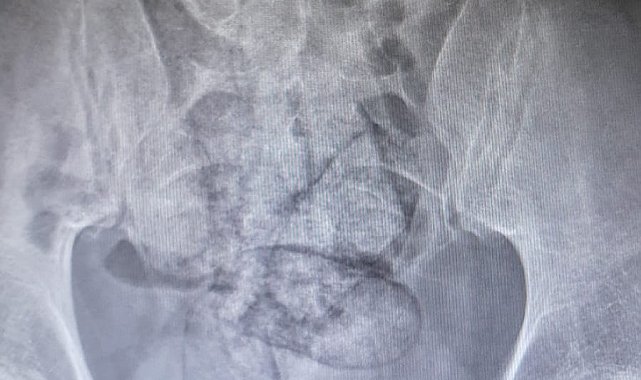

ARTVİN'de bağırsağından 350 gram metamfetamin çıkan İran uyruklu F.R. (43) gözaltına alındı.İl jandarma ekipleri, takip ettikleri İran uyruklu şüpheliyi dün saat 02.00 sıralarında Çayağzı Mahallesi'nde durdurdu. Üzerinde yapılan aramada herhangi bir olumsuzluğa rastlanmayan F.R., detaylı kontrol için hastaneye götürüldü. Artvin Devlet Hastanesi'nde tomografisi çekilen şüphelinin bağırsaklarında 10 paket halinde uyuşturucu madde taşıdığı belirlendi. Şüphelinin hayati tehlike oluşturabilecek şekilde sakladığı paketler, cerrahi müdahaleyle çıkarıldı. İncelemede paketlerin içinde toplam 350 gram metamfetamin olduğu tespit edildi.Gözaltına alınan şüpheli hakkında adli işlem başlatıldı.

İranlı şüphelinin bağırsağından uyuşturucu çıktı

ARTVİN, (DHA)- ARTVİN'de bağırsağından 350 gram metamfetamin çıkan İran uyruklu F